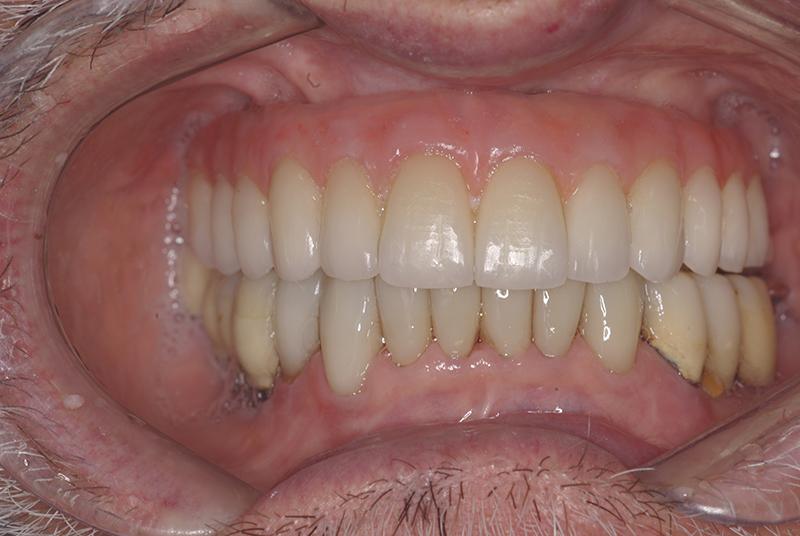

Na Clínica Pontes Odontologia, somos referência em implantes dentários em Fortaleza, oferecendo tratamentos de alta qualidade e tecnologia de ponta. Os implantes dentários são estruturas de titânio posicionadas cirurgicamente no osso maxilar ou mandibular para substituir as raízes dos dentes ausentes. Essa técnica permite a fixação de próteses personalizadas, restaurando a função mastigatória, a estética e a autoestima dos nossos pacientes.

Utilizamos a tecnologia CAD CAM, um sistema avançado que possibilita a confecção precisa das próteses dentárias diretamente sobre os implantes. Esse método inovador garante um ajuste perfeito, um resultado estético superior e proporciona muito mais conforto e durabilidade. Com o CAD CAM, nossos pacientes contam com um processo mais rápido e previsível para alcançar o sorriso desejado.